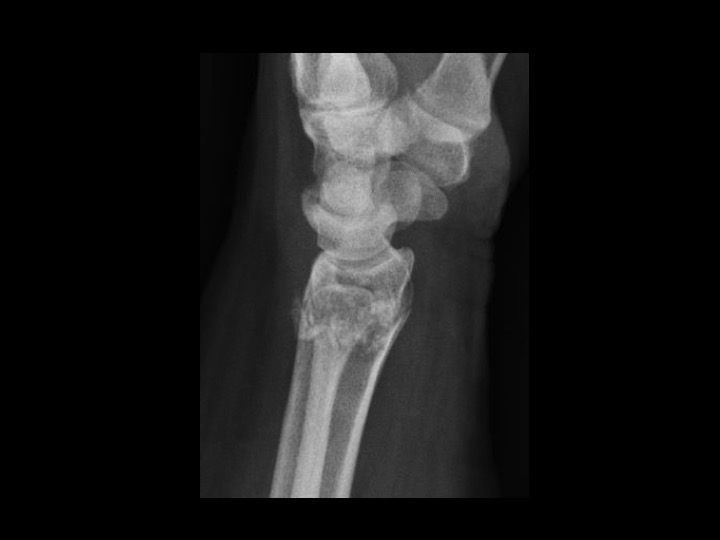

57F fell 2 weeks ago

Solitary epiphyseal enchondroma is reportedly rare (in the attached article, the incidence is 4%, higher than other series). This came to attention because of fracture after fall, though I would characterize this as a pathologic fracture, since the lesion occupies most of the DR with endosteal scalloping. In the attached article, there was no aggressive behavior on limited follow up. The radiographic appearance is non-aggressive. Is that sufficient to assume this is an epiphyseal enchondroma, not requiring close and continued imaging follow up? Or does the epiphyseal location raise suspicion and require continued surveillance after the fracture has healed? I imagine this might require currettage and grafting, at which time there would be pathology...but this is being followed currently.

enchondroma ( RID4128 )